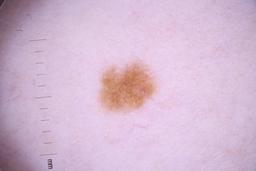

ISIC_4077341

- Challenge 2020: Training

- IP_1969685 IL_9238622

Clinical

| Field | Value |

|---|---|

| acquisition_day | 1 |

| age_approx | 50 |

| anatom_site_1 | Trunk |

| anatom_site_2 | Anterior trunk |

| concomitant_biopsy | False |

| dermoscopic_type | contact non-polarized |

| diagnosis_1 | Benign |

| diagnosis_confirm_type | serial imaging showing no change |

| family_hx_mm | False |

| image_type | dermoscopic |

| lesion_id | IL_9238622 |

| patient_id | IP_1969685 |

| personal_hx_mm | True |

| sex | male |